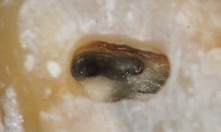

Dr. Brüsehaber: Ich beginne die Trepanation der Pulpakammer sehr gern mit einer Diamantkugel (z. B. 6801L, Komet) (Abb.1). Wenn ich damit das Pulpencavum direkt eröffnen kann, gilt es, im nächsten Behandlungsschritt die Hartsubstanzüberhänge abzutragen, um einen „straight line access“ zu den Wurzelkanälen zu schaffen (Abb. 2 und 3). Ein geradliniger Zugang ist essentiell für alle weiteren Behandlungsschritte. Mit ausreichender Erfahrung und unter Verwendung eines Operationsmikroskops ist es möglich, das Wurzelkanalsystem auch über eine sehr kleine Zugangsöffnung zu behandeln.